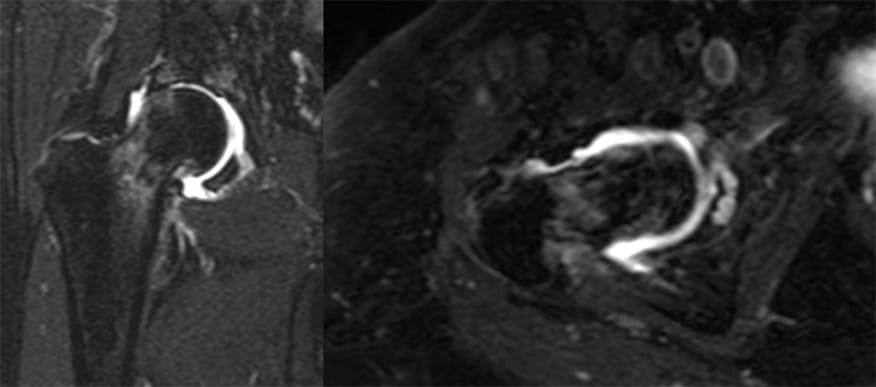

As a complementary method of diagnosis, we requested an MRI. The following week she returned with an MRI, using an elbow crutch on the left hand due to increased pain (Visual Analog Scale 9) and intolerance to weight bearing. The MRI showed an increase in synovial fluid in the right hip (Figure 2). With suspicion of septic arthritis, we performed an arthrocentesis in the operating room and requested a blood test with infection related makers (normal values: White Blood Cell Counts < 9000 mm3, Erythrocyte sedimentation rate < 16mm/1st hour, C-reactive Protein <0.3mg/dL). Results were compatible with infection: WBC 16500mm3, ESR:26 and CRP: 0.1mg/dL. We decided to perform an arthroscopic lavage and collection of samples for bacteriological culture.